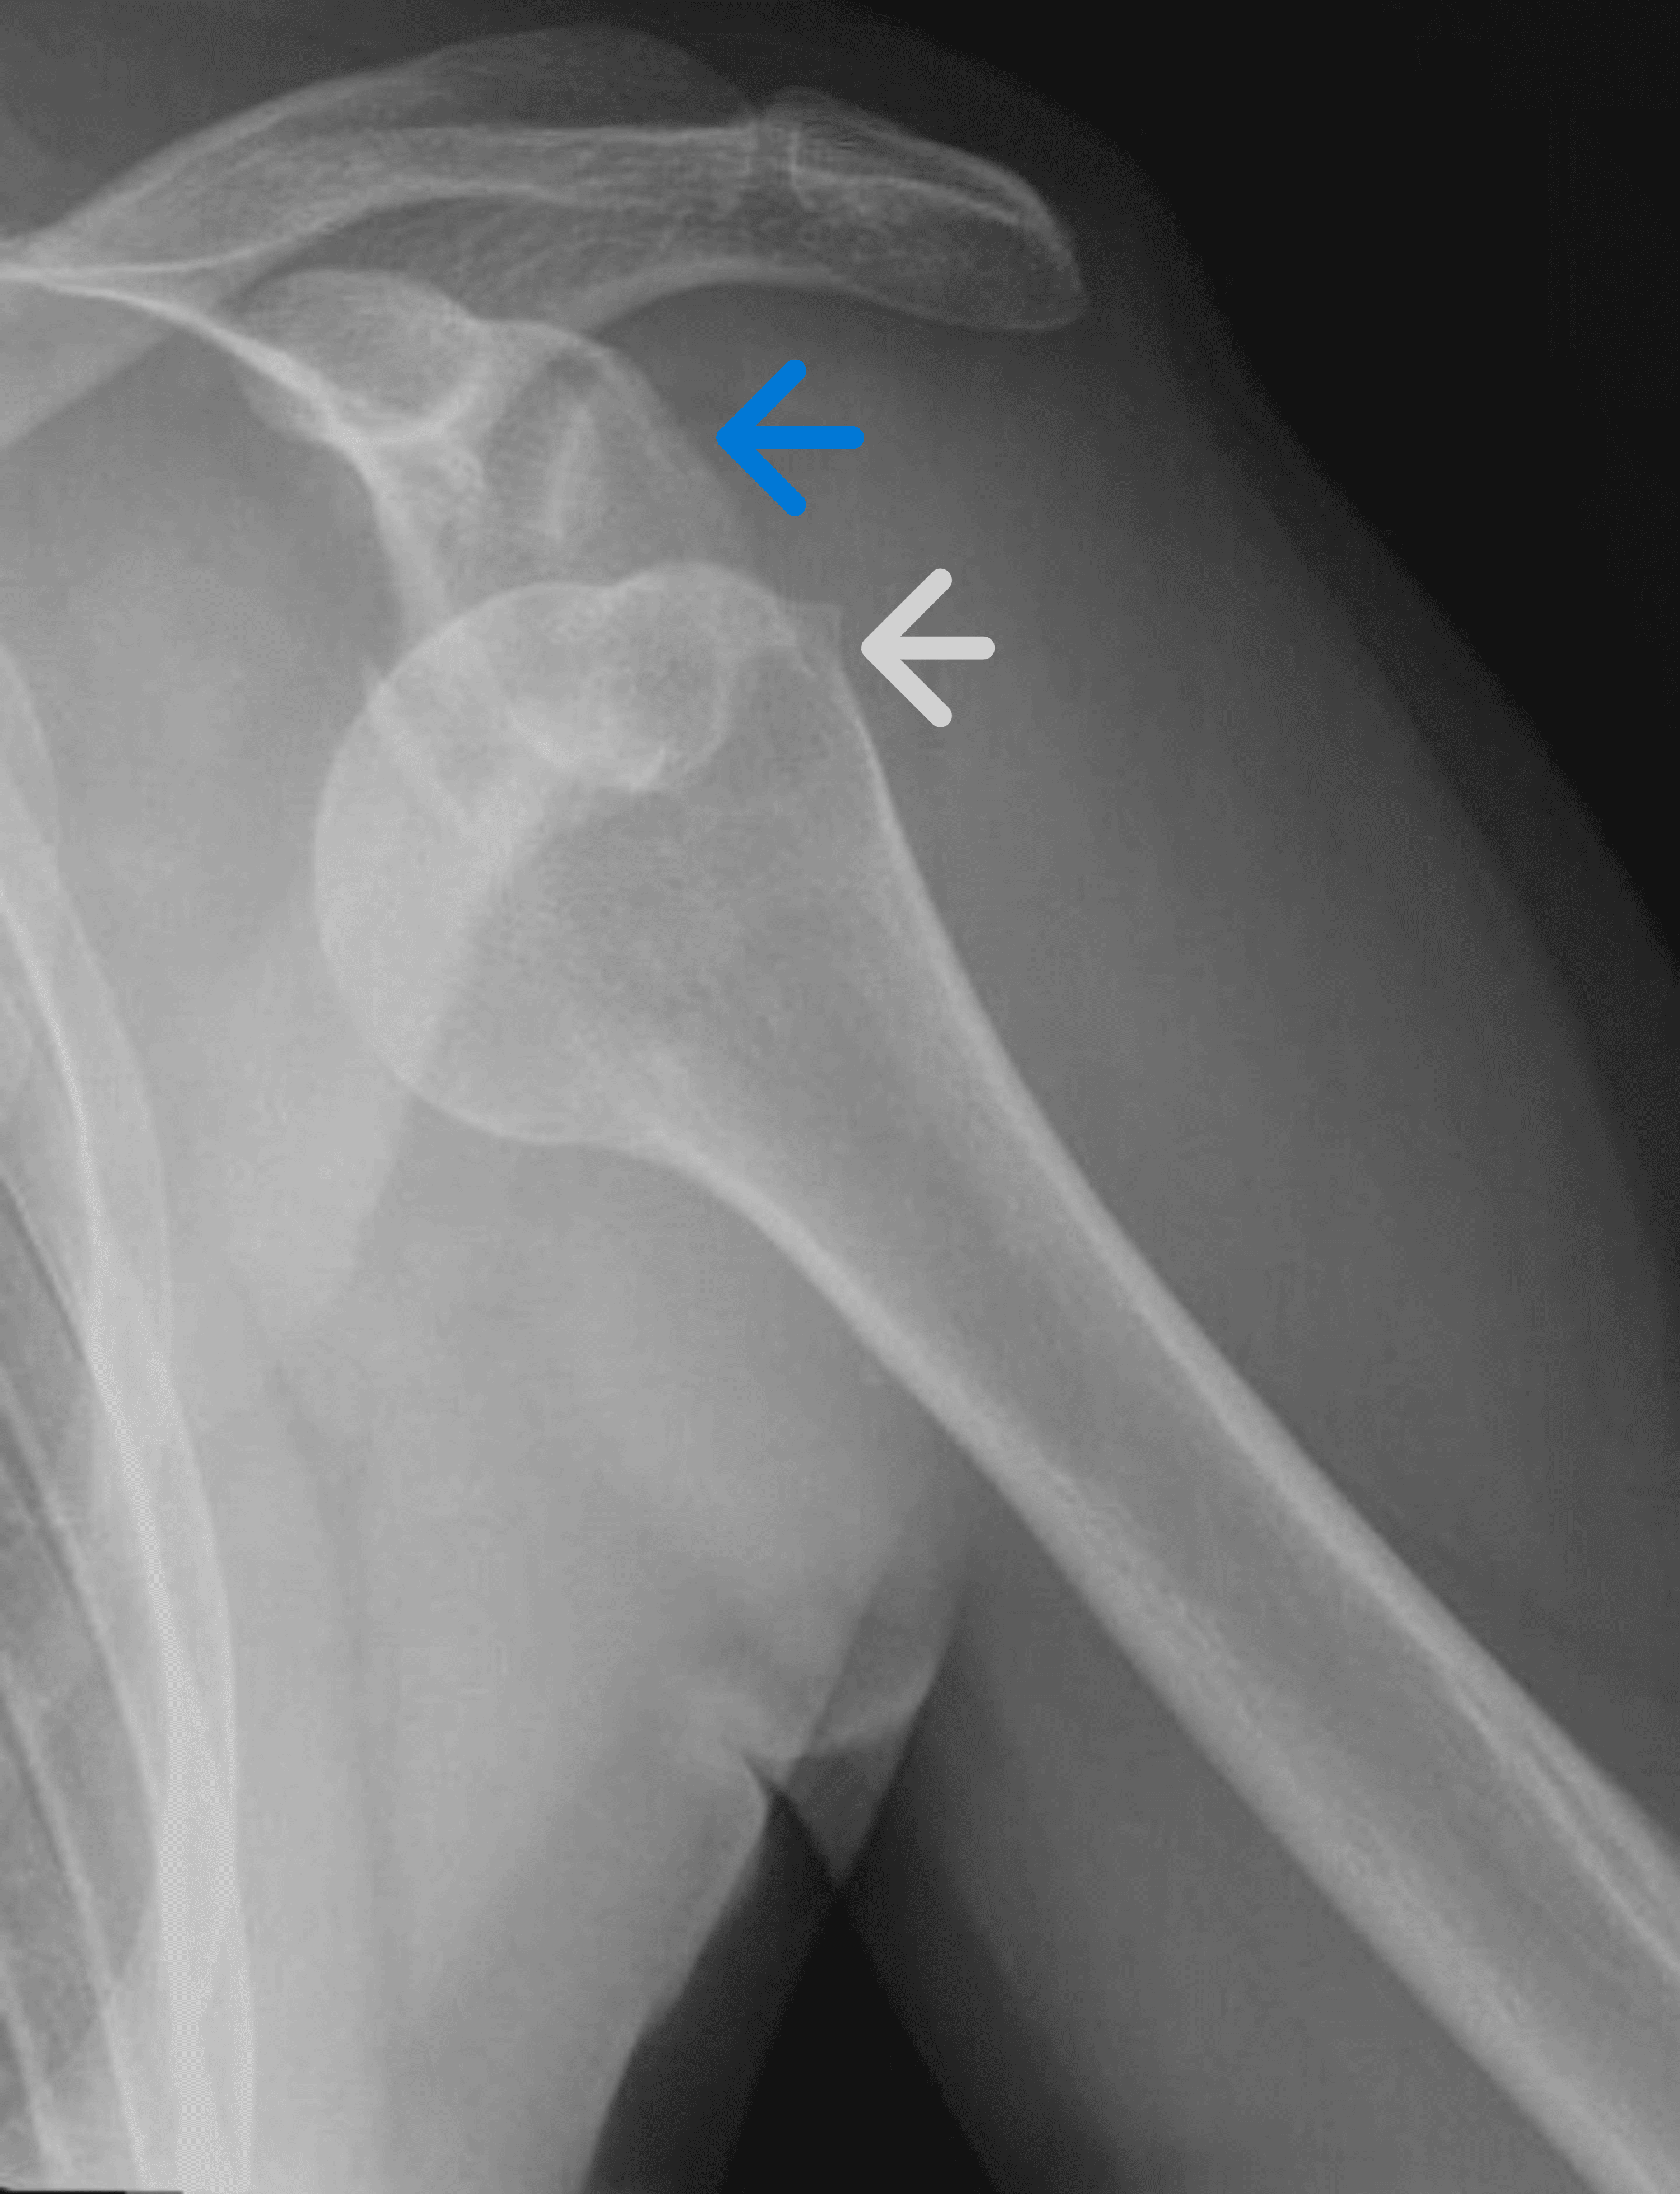

Shoulder Dislocation and Hill Sach’s Lesion —

Shoulder Dislocation and Hill Sach’s Lesion — Shoulder Dislocation Mdm initial consideration in this patient included shoulder dislocation, fractures of the humerus, clavicle and. shoulder dislocations are the most common of all major joint dislocations and frequently present to clinics and. At the end of this hour. The dislocation may anteriorly, posteriorly, inferiorly, or anterior. Waking up at night during sleep. shoulder dislocations are the most common. Shoulder Dislocation Mdm.